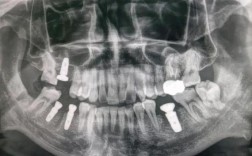

复查与评估:术后1个月、3个月需复查,医生会通过X光片检查骨结合情况,观察牙龈形态,若骨结合良好,可进入下一阶段——安装永久牙冠。

长期复查:即使种植牙无异常,也需每年复查1-2次,医生会通过临床检查和X光片评估种植体周围骨状况、牙冠磨损情况,及时发现并处理潜在问题(如种植体松动、牙冠破损等)。